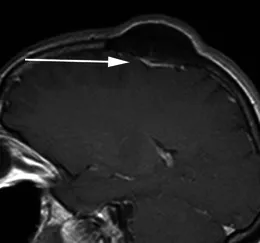

一名49歲女性患者,因頭皮腫塊就診

一名49歲女性患者,因頭皮腫塊就診。其矢狀位增強(qiáng)后T1加權(quán)序列顯示,左側(cè)頂骨可見一明顯骨質(zhì)增生灶,病灶主體向顱外突出。緊鄰骨性病變下方,可見一薄片狀、均勻強(qiáng)化的軸外軟組織影(箭頭所示),符合扁平型腦膜瘤的影像學(xué)特征,后經(jīng)手術(shù)病理證實(shí)。